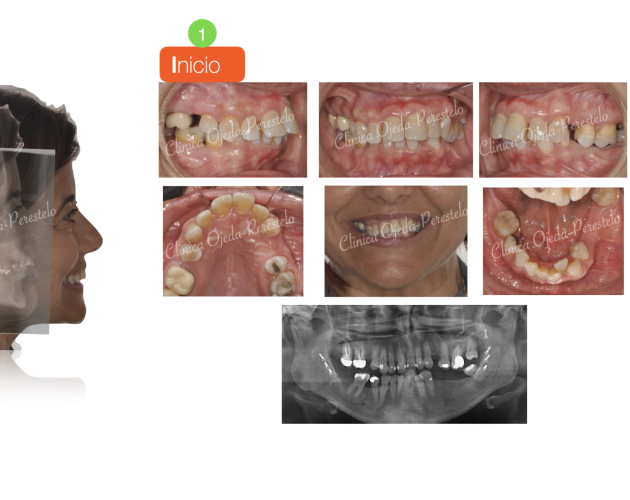

Premolar Mandibular Retenido (35) Casos de Éxito - Niños - Dientes Retenidos